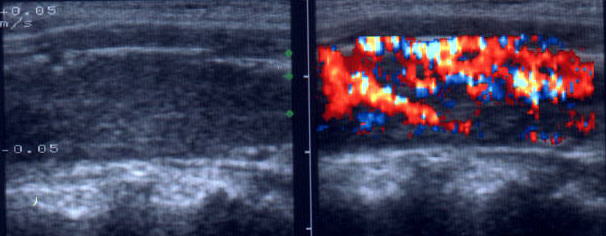

Acelasi

pacient. La doppler color, vascularizatie bogata, difuza in toata glanda

Femeie de 44 ani. Tireotoxicoza in m. Graves.

Marcata crestere a velocitatii cu picul sistolic (1,44 m/s).